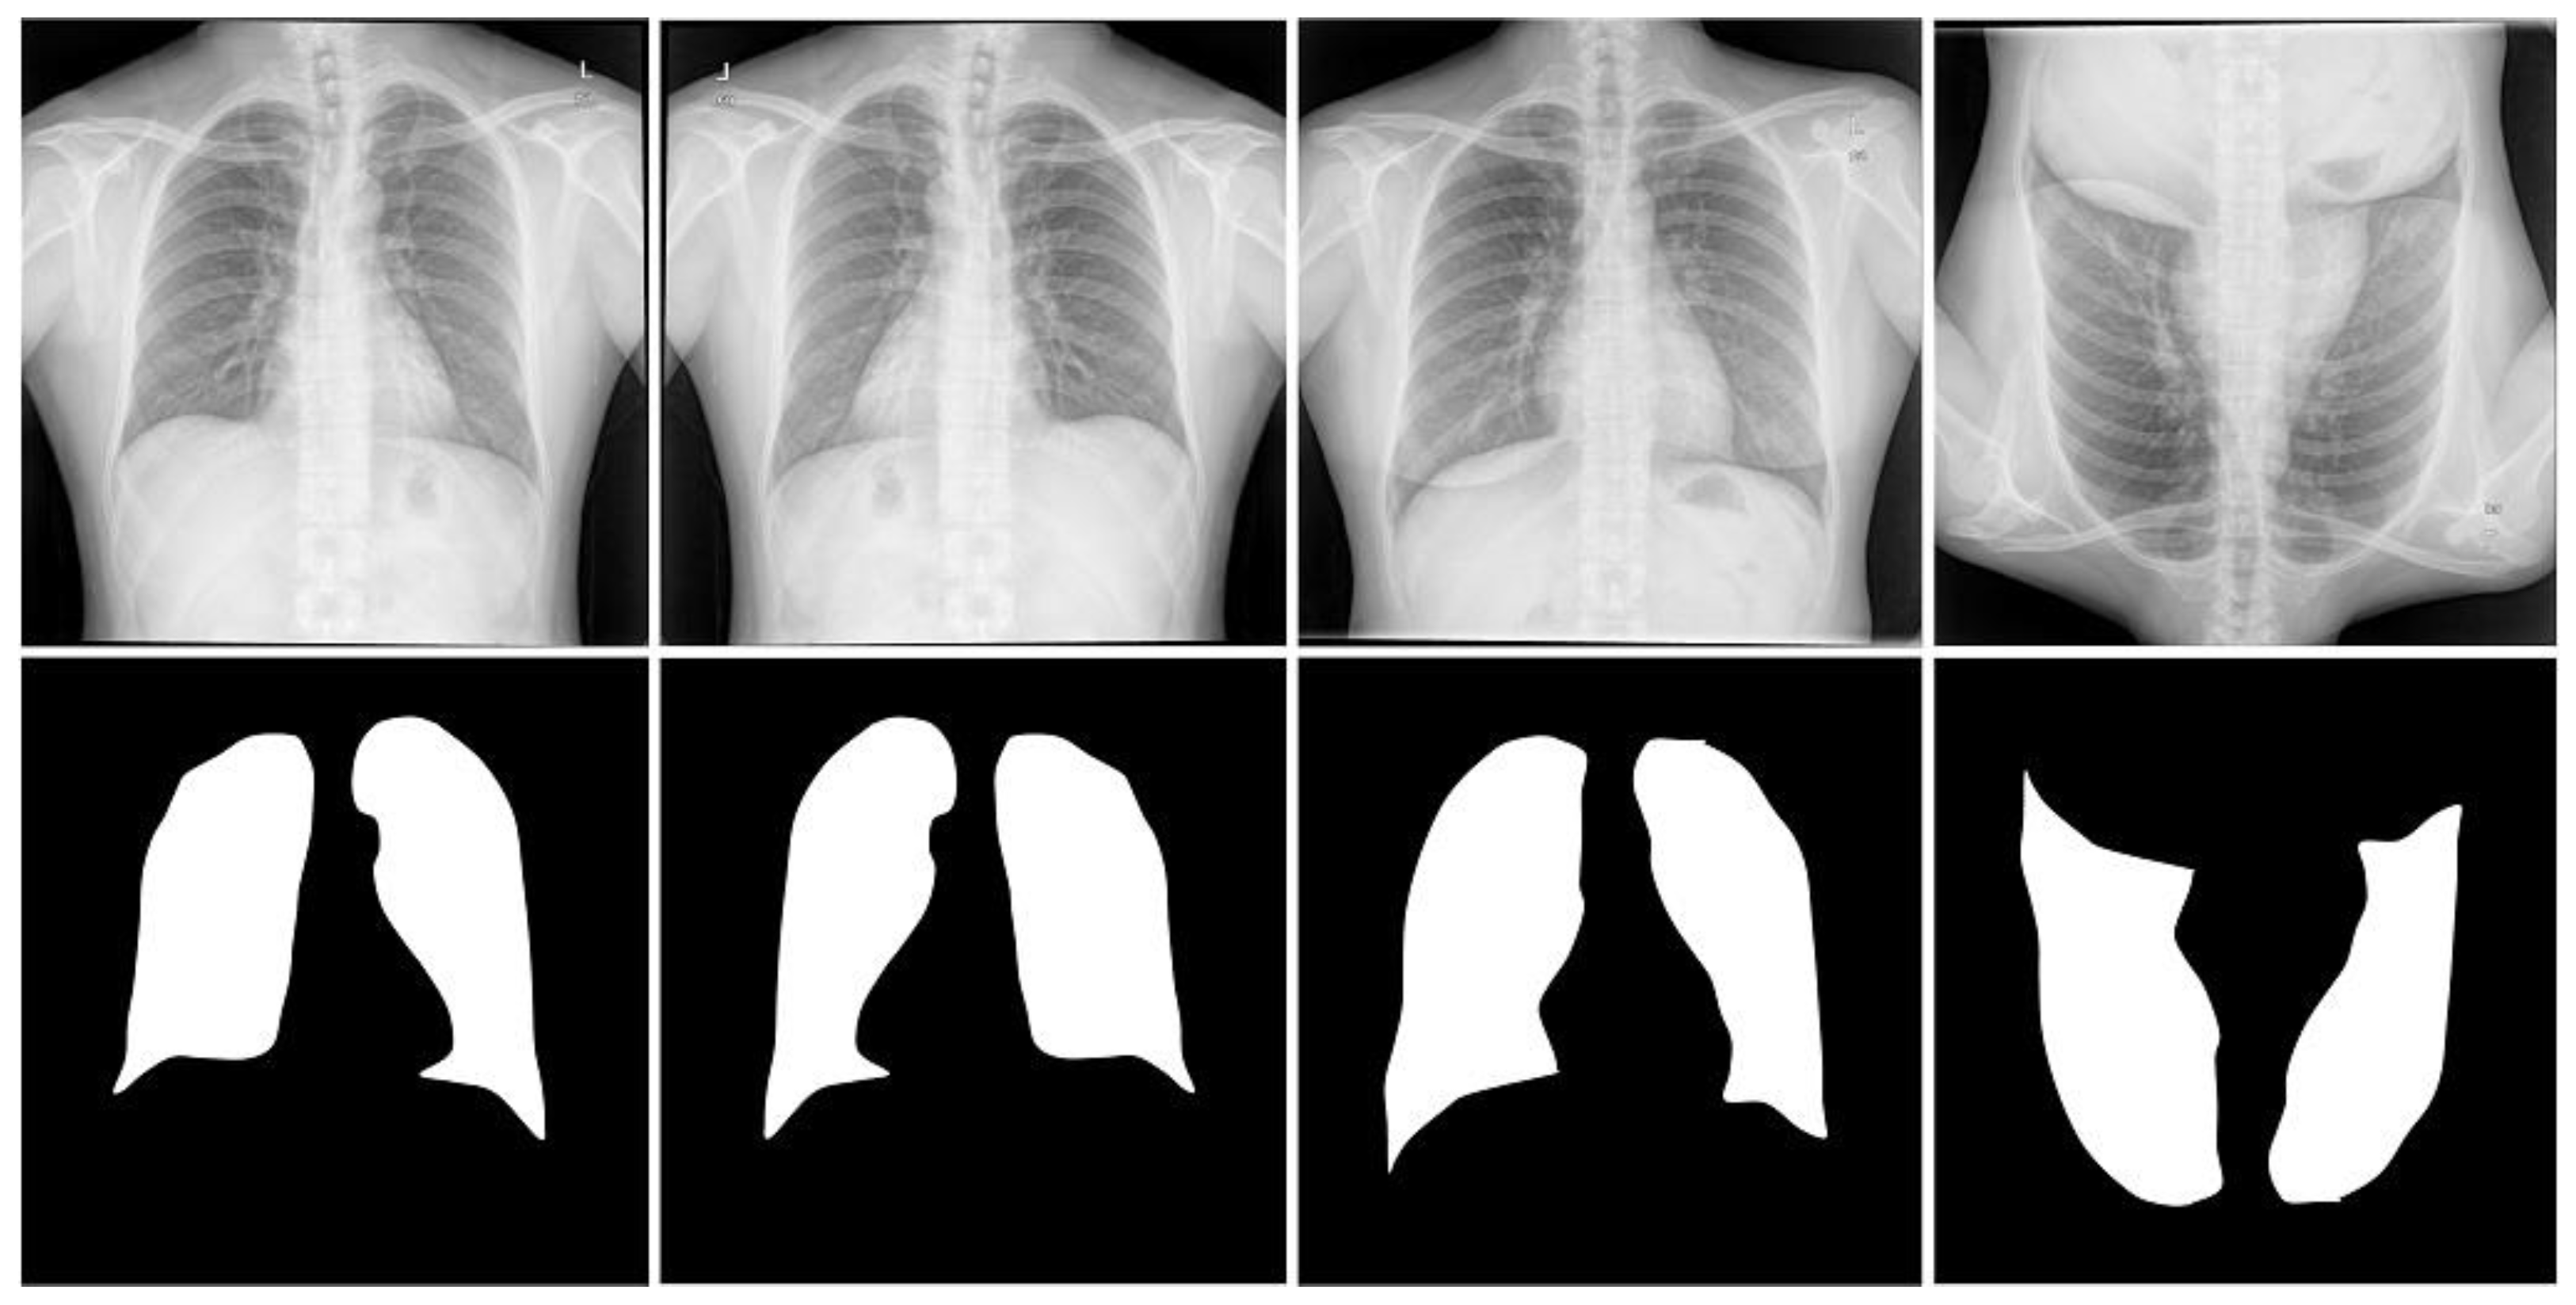

Shenzhen dataset [18]. This dataset is a collaboration between the Third People’s Hospital of Shenzhen, Guangdong, China, and the National Library of Medicine of Maryland, USA. It contains 662 radiographic images of the human chest region; each CXR radiograph is a single-channel grayscale image with a color depth of 8 and an average resolution of 326 radiographs healthy subjects and 336 from patients with tuberculosis. We used this dataset supervised and labeled by professional radiologists, which was provided by Jaeger et al. [18]. For the Shenzhen dataset, we used simple three-fold machine rotations and a simple three-fold flip data enhancement strategy, and trained the original image data together in the expanded dataset, which was expanded to seven times the original size, containing 4634 images. We use 3710 images as training cases, 336 images as validation cases, and 336 images as test cases. Table 1 shows the CXR and its specification summary of the X-ray film images of the three data sets after data enhancement, and the original and enhanced example images of the three data sets are shown in Figure 3, Figure 4 and Figure 5.

Figure 5.

Images and masks of the Shenzhen dataset.